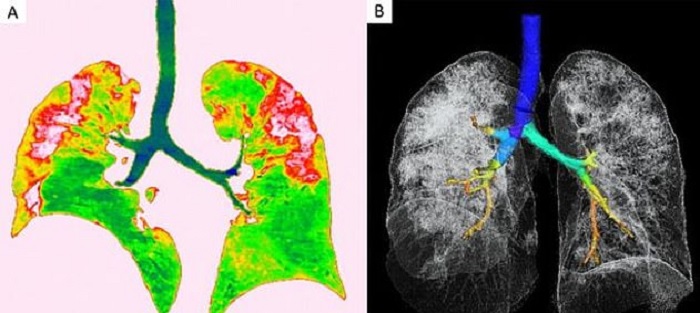

أخيرا صور الأشعة أصبحت ملونة